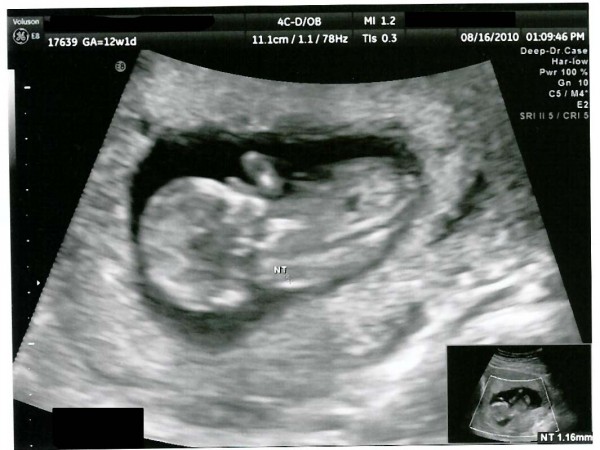

So I'm still pregnant.. yay 3 weeks past the point of my miscarriage, and 100% different than the last pregnancy.. there's actually a baby in there I'm 12 weeks and 3 days along. My due date is February 27...aaaaand it's a GIRL!! Pretty sure at least. I had an ultrasound on Monday and the doctor is 80% sure it's a girl. I think he's going by a gender theory, but he's the professional, and I have a strong feeling it's a girl anyway. So do a few other people.. except my mom, but that's a good indication that it really is a girl, because she has never been right!

Here's a picture of my little peanut